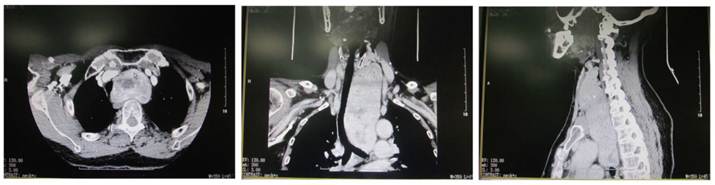

Figure 3

CT of giant nodular goiter. The thyroid was enlarged and uneven enhancement was noted. Surrounding organs were pushed toward right side.

Plain CT scan showed the lesion was focal and enhancement CT scan revealed enhancement of different extents. There were 46 patients with esophageal compression and 25 had tracheal compression (Figure 3). Cervical X ray can reveal the tracheal compression, dislocation or stenosis. Positive lateral X ray can reveal the degree of tracheal compression. The difference in tracheal diameter between inspiration and expiration of >5 mm can be used to diagnose tracheomalacia. Retrosternal giant goiter was manifested by mass with different densities in the mediastinal region, and enhancement CT showed uneven enhancement accompanied by compression of adjacent organs (Figure 4).